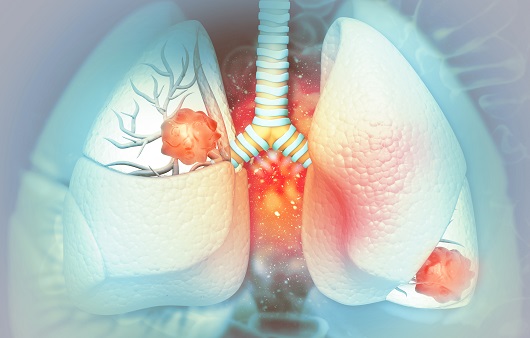

폐암 초기증상 - 8. 기침

기침은 폐에 염증이나 종양이 발생할 때 많은 사람들이 경험하는 일반적인 증상입니다. 그러나 기침은 폐암의 흔한 조기 경고 신호이기도 하며, 환자의 75%가 기침을 경험한다고 보고했습니다. 기침이 지속되고 다음과 같은 증상이 나타나면 폐암의 조기 경고 신호로 간주해야 합니다.

폐암 초기증상 - 11. 호흡곤란

폐가 영향을 받으면 약간의 운동에도 숨이 가빠지고 호흡 곤란을 경험할 수 있습니다. 암세포의 성장으로 인한 폐 기능 상실로 인해 일부 사람들은 호흡 곤란을 겪을 수 있으며 흉막 삼출, 폐 붕괴 및 상기도 폐쇄로 인해 호흡이 어려워질 수 있습니다. 가벼운 증상을 무시하기 쉽지만 무시하면 통제할 수 없을 정도로 커질 수 있으므로 신속하게 검사를 받아야 합니다.